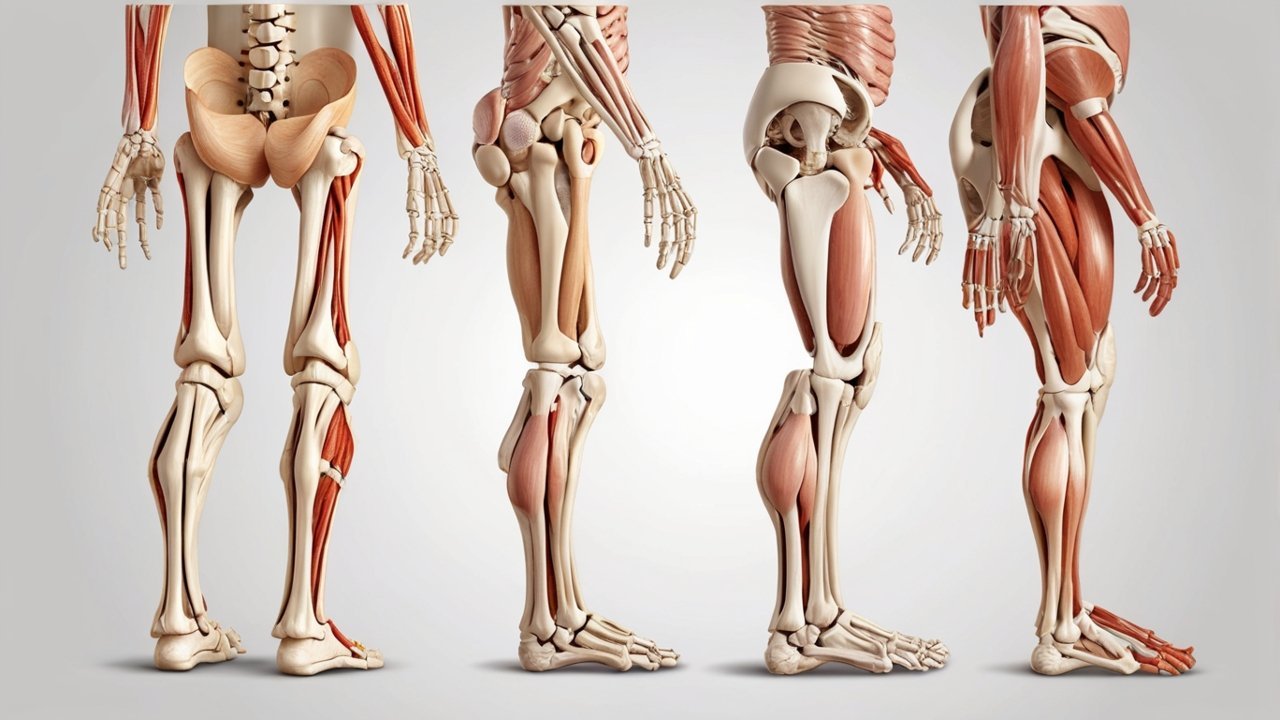

Diagnostic Tests and Imaging for Accurate Arthritis Evaluation

After the initial consultation, arthritis care specialists may recommend diagnostic tests to confirm or clarify a diagnosis. These tests are chosen carefully and are not ordered unless clinically useful.

Common diagnostic tools include:

-

Blood tests to detect inflammation or autoimmune markers

-

X-rays to assess joint space and structural changes

-

Ultrasound or MRI for soft tissue evaluation

According to studies indexed on PubMed, early imaging and laboratory evaluation improve diagnostic accuracy and guide more effective treatment decisions. These tests also establish a baseline, making it easier to track disease progression over time.